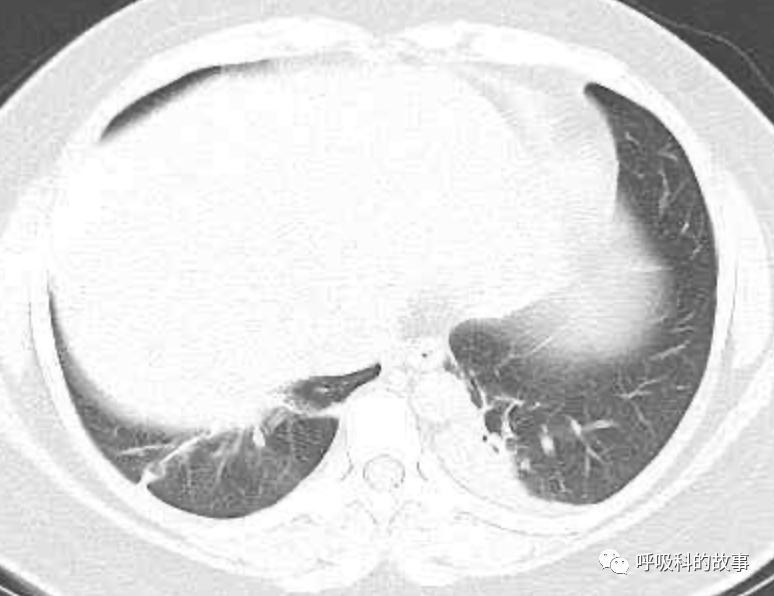

患者发热后行胸部CT检查(6月21日,住院第13天),可见两下肺有条片影,当时考虑是肺炎引起的发热。

可是在6月26日(往院第18天)仍持续发热的情况下复查肺部CT,肺部病灶已明显吸收了。那么患者发热的原因到底是什么呢?为什么患者高热的情况下血白细胞不升反降,C反应蛋白也没有明显增高?这个时候消化科医生也迷茫了,这可怎么办?于是请感染科和呼吸科医生一起会诊,共商计策。